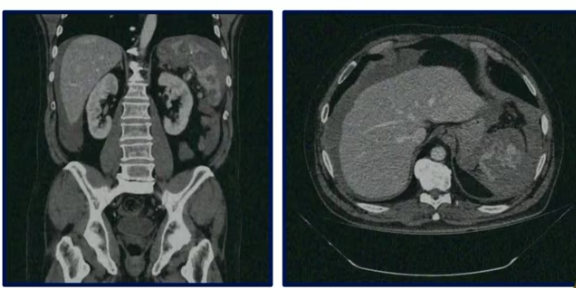

Paciente pós trauma contuso (fechado) estável com hematúria e imagem abaixo * Conduta?

* Trata-se de um hematoma subcapsular renal, ou seja lesão de viscera sólida * Todavia, mesmo com isso, estando o paciente estável, a conduta é sempre conservadora com vigilância criteriosa * Caso haja piora persistente, pode se fazer arteriografia com embolização se blush na fase aguda do trauma ou sangramento tardio * Se paciente instável, provavelmente vai apresentar **hematoma pulsátil ou em expansão**, logo, fazer cirurgia

TC ABDOMINAL E PELVICO TRIFÁSICO * Fases * O que é avaliado em cada uma delas

Sempre soliticar após trauma abdominal **1 fase (sem contraste)** * Avaliar se há sangramento ativo * O sangue é hiperatenuante (branco) (presente na imagem) **2 fase (arterial)** * Aorta e outras artérias ficam brancas * Verificar se não há extravazamento de sangue! (não está presente na imagem acima) * Cortex fica branco, mas a medula continua cinza **3 fase (portal)** * Rim e veias inteiramente contrastadas (brancas) * Se alguma área estiver preta, indica lesão vascular **4 fase (extretora)** * Contraste nos calices * Verificar se há extravasamento de contraste